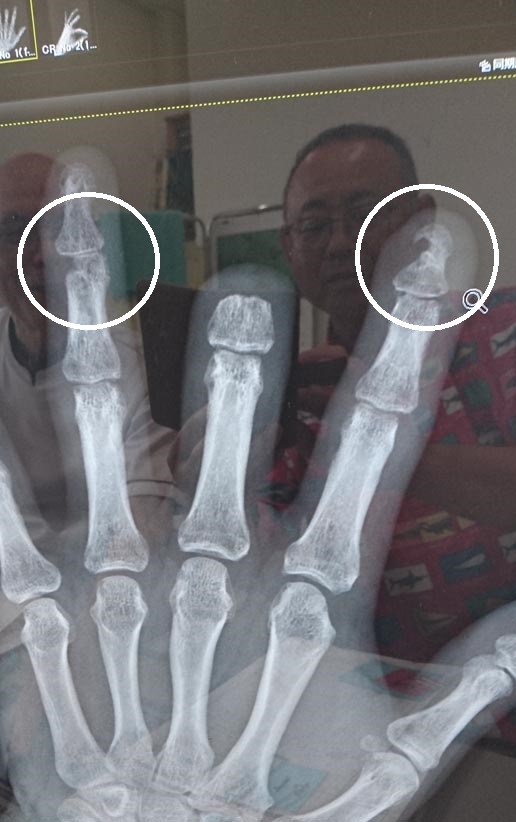

| 手術後のレントゲン画像 | 現在のレントゲン画像 |

診察で院長先生と手術後の画像をパソコンの画面で比較して 骨の付き具合を確認する 左手人差し指・示指末節骨骨折、中指・不全切断(欠損) 薬指・第1間接環指不全切断 |

「大分、骨が付いてきているけど、まだまだだね」 「若いともっと早く骨が基質形成してくるんだけどね・・・」 「そんなこと言われても・・・・・」 パソコンの画面に映り込んでいるハゲ頭が院長 |